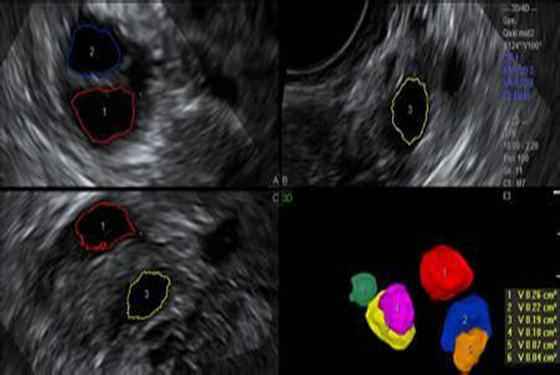

若要问卵泡监测什么时候做最合适,医生建议根据具体的月经周期进行监测,每个女性的月经周期有所不同,排卵的时间也各自有差异。卵泡监测一般在月经周期第9-10天时进行,每隔1-2天去医院用B超监测一次,医生通过几次B超检测后,就可以看到卵泡慢慢长大、成熟以及排卵的全过程。至于,优势卵泡什么时候会出现,这是因人而异的,通常月经周期28天的女性,在监测的第9-12天内优势卵泡会出现。

卵泡监测,不是一个短期能看到结果的检查,做这种检查时一定要注意连续性,不能一看到优势卵泡出现就停止监测,一定要坚持到确认排卵或卵泡发育不良后为止。另外,卵泡监测不是做一次就可以的,女性要根据自己的月经情况,从来月经第1天开始直到第11天,隔天需要去医院用B超进行监测,这个过程很漫长,可能长达三个月之久,这样医生才能找出你的规律哦。